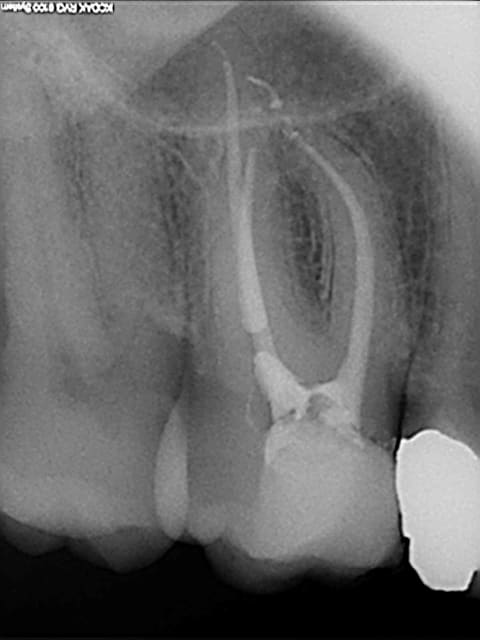

petit jeu:

A vous de trouver quelle endo a été faite au thermafill et laquelle au gutta condensor?

Endo 2 : Thermafil

En général le thermafil est moins radioopaque que la gutta thermocondensée, donc j'aurais plutôt dit la 1, mais c'est vrai que sur la 2 tu as probablement quatre canaux, ce qui augmente la densité et les bouts font un peu "pointu" laissant penser que les tuteurs se sont peut être un peu décalés...

1/Thermafill( on croit apercevoir les tuteurs)

2/gutta condensor ,( je crois voir une spirale dans l' un des canaux mesiaux! )

1:thermafill

endo1 a été fait au gutta condensor

endo 2 au thermafil.

Seul Marc a eu du nez la dessus. ;-)

Comme quoi, radiologiquement, difficile de faire le distinguo entre ces deux méthodes.

C'est la rectitude de l'obturation dans le dernier millimètre apical, surtout sur le canal distal qui m'a mis sur la voie.